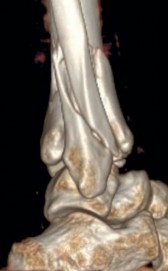

Temporary ankle-spanning external fixation was used to stabilize the fracture and soft tissues. X-rays taken after external fixation showed improved alignment and allowed for better understanding of the fracture pattern (Fig 2.2-2). Computed tomographic (CT) scanning with 3D reconstruction was performed for precise assessment of the fracture pattern of the tibial plafond. The CT revealed displaced fragments with a resultant intraarticular step-off and gap. The distal tibial metaphyseal fracture was multifragmentary. In addition, an associated long oblique fibular fracture was present (Fig 2.2-3).

Fig 2.2-3a–h A CT scan with 3D reconstruction.

a–d Sagittal (a–b), coronal (c), and axial (d) images demonstrate displaced posterior, anterolateral, and medial fracture fragments resulting in intraarticular step and gap. The incongruent tibiotalar joint is best appreciated on the sagittal scan.

e–h The 3D reconstructed images show the external fracture anatomy and general alignment.